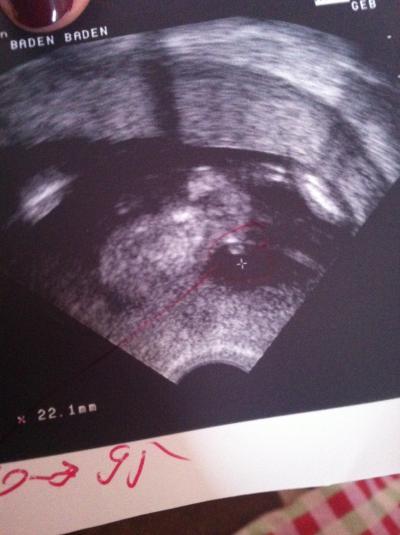

Hallo meine Lieben! Ich bin ein wenig ratlos und hoffe auf eure Hilfe Die Vertretung meines Frauenarztes meinte in der 17.SSW das er da ganz sicher einen jungen erkennt auf dem US Bild. Jetzt meine Frage: Seht ihr das auch so? Ist dieser runde Punkt wirklich ein Hoden? Ist das schon soooo ausgeprägt in der Zeit? Kommt mir gigantisch vor Ich hoffe ihr haltet mich nicht für völlig doof Er hat den Zwerg auf den Bildern quasi auf zwei Bildern aufgeteilt und das ist wohl der untere Teil mit Popo und Beinchen. Das im roten Kreis sollte der wohl der Pipi sein :) Ich wäre euch wirklich soooo dankbar über eure Meinungen!! Viele Grüße Lilli

Jep, sieht nach Junge aus. Hoden und Pipimatz dran, also ich seh das zumindest so